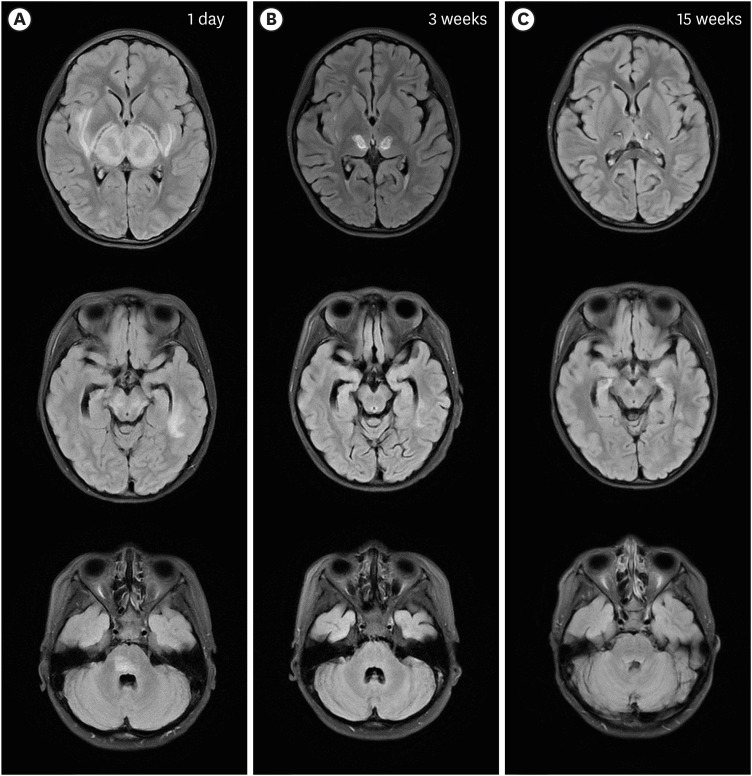

Coronavirus disease 2019 (COVID-19), caused by severe acute respiratory syndrome coronavirus 2, presents primarily with respiratory symptoms. However, children with COVID-19 are usually asymptomatic or mild acute symptoms and also neurological manifestations have also been observed. We report the case of a 7-year-old girl who presented with high fever and altered mental status, leading to a diagnosis of COVID-19 and acute necrotizing encephalopathy (ANE). The patient received intensive medical care in the intensive care unit and subsequently underwent rehabilitation programs due to neurological functional sequelae. Neurological complications in COVID-19, including ANE, may result from potential viral nerve involvement, cytokine storms, and the blood-brain barrier disruption. Early rehabilitation plays a pivotal role in managing COVID-19-related neurological complications and enhancing patients' functional outcomes. Further research is essential to gain a better understanding of the mechanisms and treatment strategies for neurological manifestations in pediatric COVID-19 patients, particularly those with multisystem inflammatory syndrome in child.